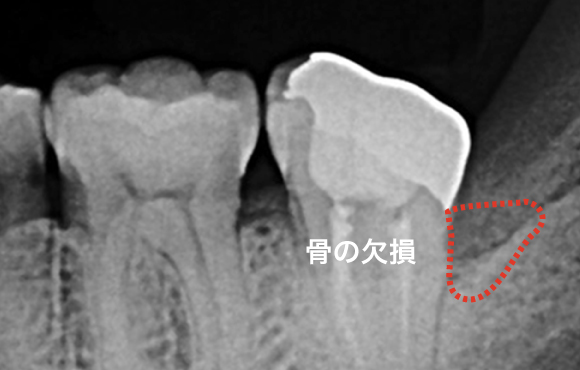

進行した歯周病は初期治療では治らない場合もあります。歯周ポケットが深いところは器具が届かないところがあるからです。溝が深くなればなるほど器具の到達率な低下し歯石は取り残しになります。

歯周初期治療後改善しない場合、歯茎を切開して深いポケットの歯石を取ります。

歯肉弁剥離掻把術

骨に大きな段差がある場合は

骨に大きな段差がある、骨をなだらかにするには限界があります。